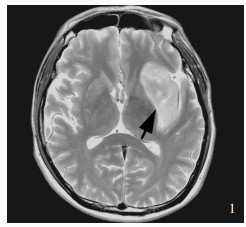

Sun GC , Chen XL , Hou YZ , Yu XG , Ma XD , Liu G , Liu L , Zhang JS , Tang H , Zhu RY , Zhou DB , Xu BN . Image - guided endoscopic surgery for spontaneous supratentorial intracerebral hematoma. J Neurosurg, 2017, 127: 537- 542.

doi: 10.3171/2016.7.JNS16932